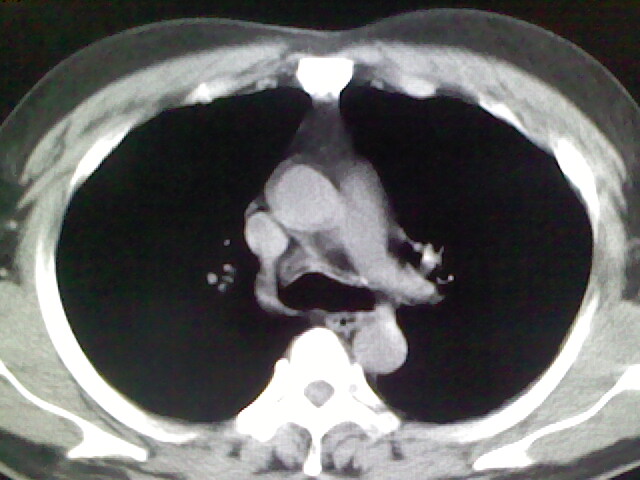

标题: CT17932:临床怀疑肺栓塞

男,34岁,自觉右侧胸痹,胸闷3天余

未见明显异常。图像上看此患者比较肥胖,建议查下心超

肺部大致正常,有可能给心脏需作个检查。